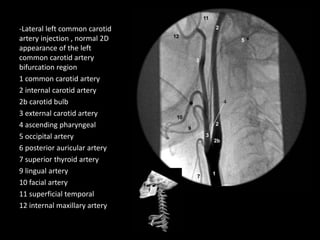

-Lateral left common carotid

artery injection , normal 2D

appearance of the left

common carotid artery

bifurcation region

1 common carotid artery

2 internal carotid artery

2b carotid bulb

3 external carotid artery

4 ascending pharyngeal

5 occipital artery

6 posterior auricular artery

7 superior thyroid artery

9 lingual artery

10 facial artery

11 superficial temporal

12 internal maxillary artery